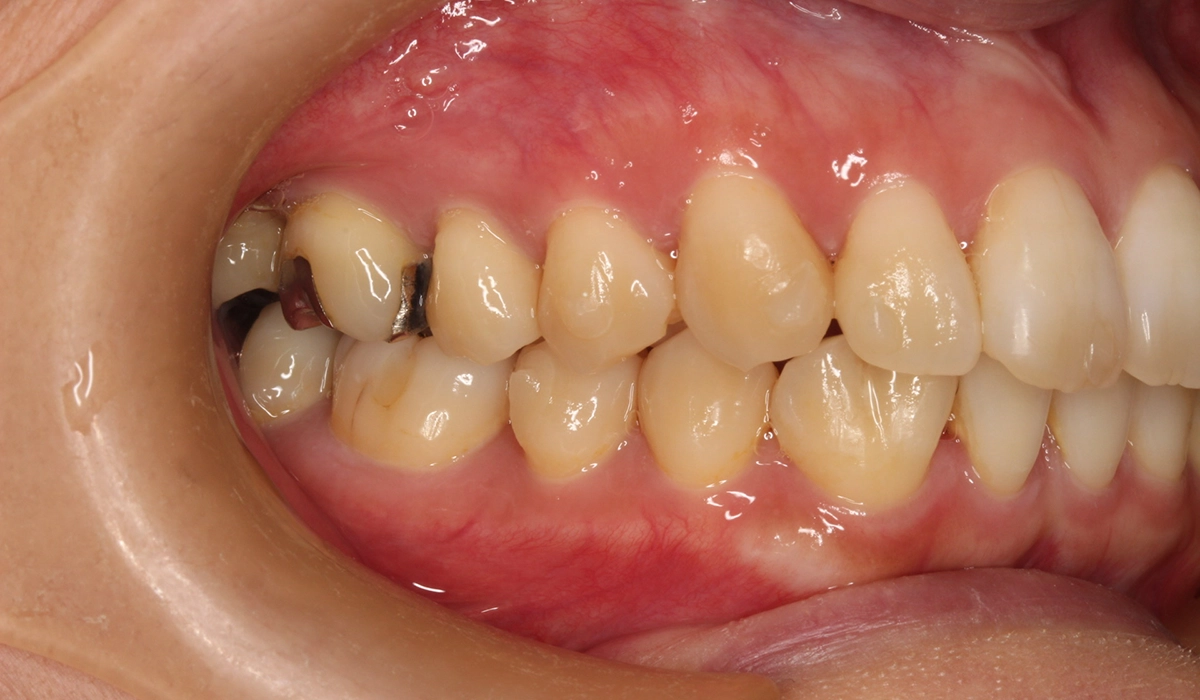

術前:右側

術後:右側